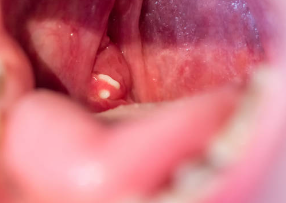

5. 가시적인 결석: 입을 벌렸을 때 편도선에 노란색 또는 흰색의 작은 결석이 보일 수 있습니다.